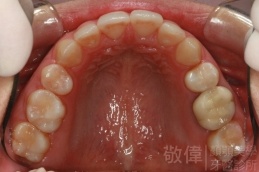

矯正前-上   矯正前-下

矯正後-上   矯正後-下

上顎暴牙且牙齒極度混亂,經由矯正之後,臉型大幅度改善,牙齒的排列更加的整齊健康。相較於之前眼神充滿精神,自信心展現無遺。